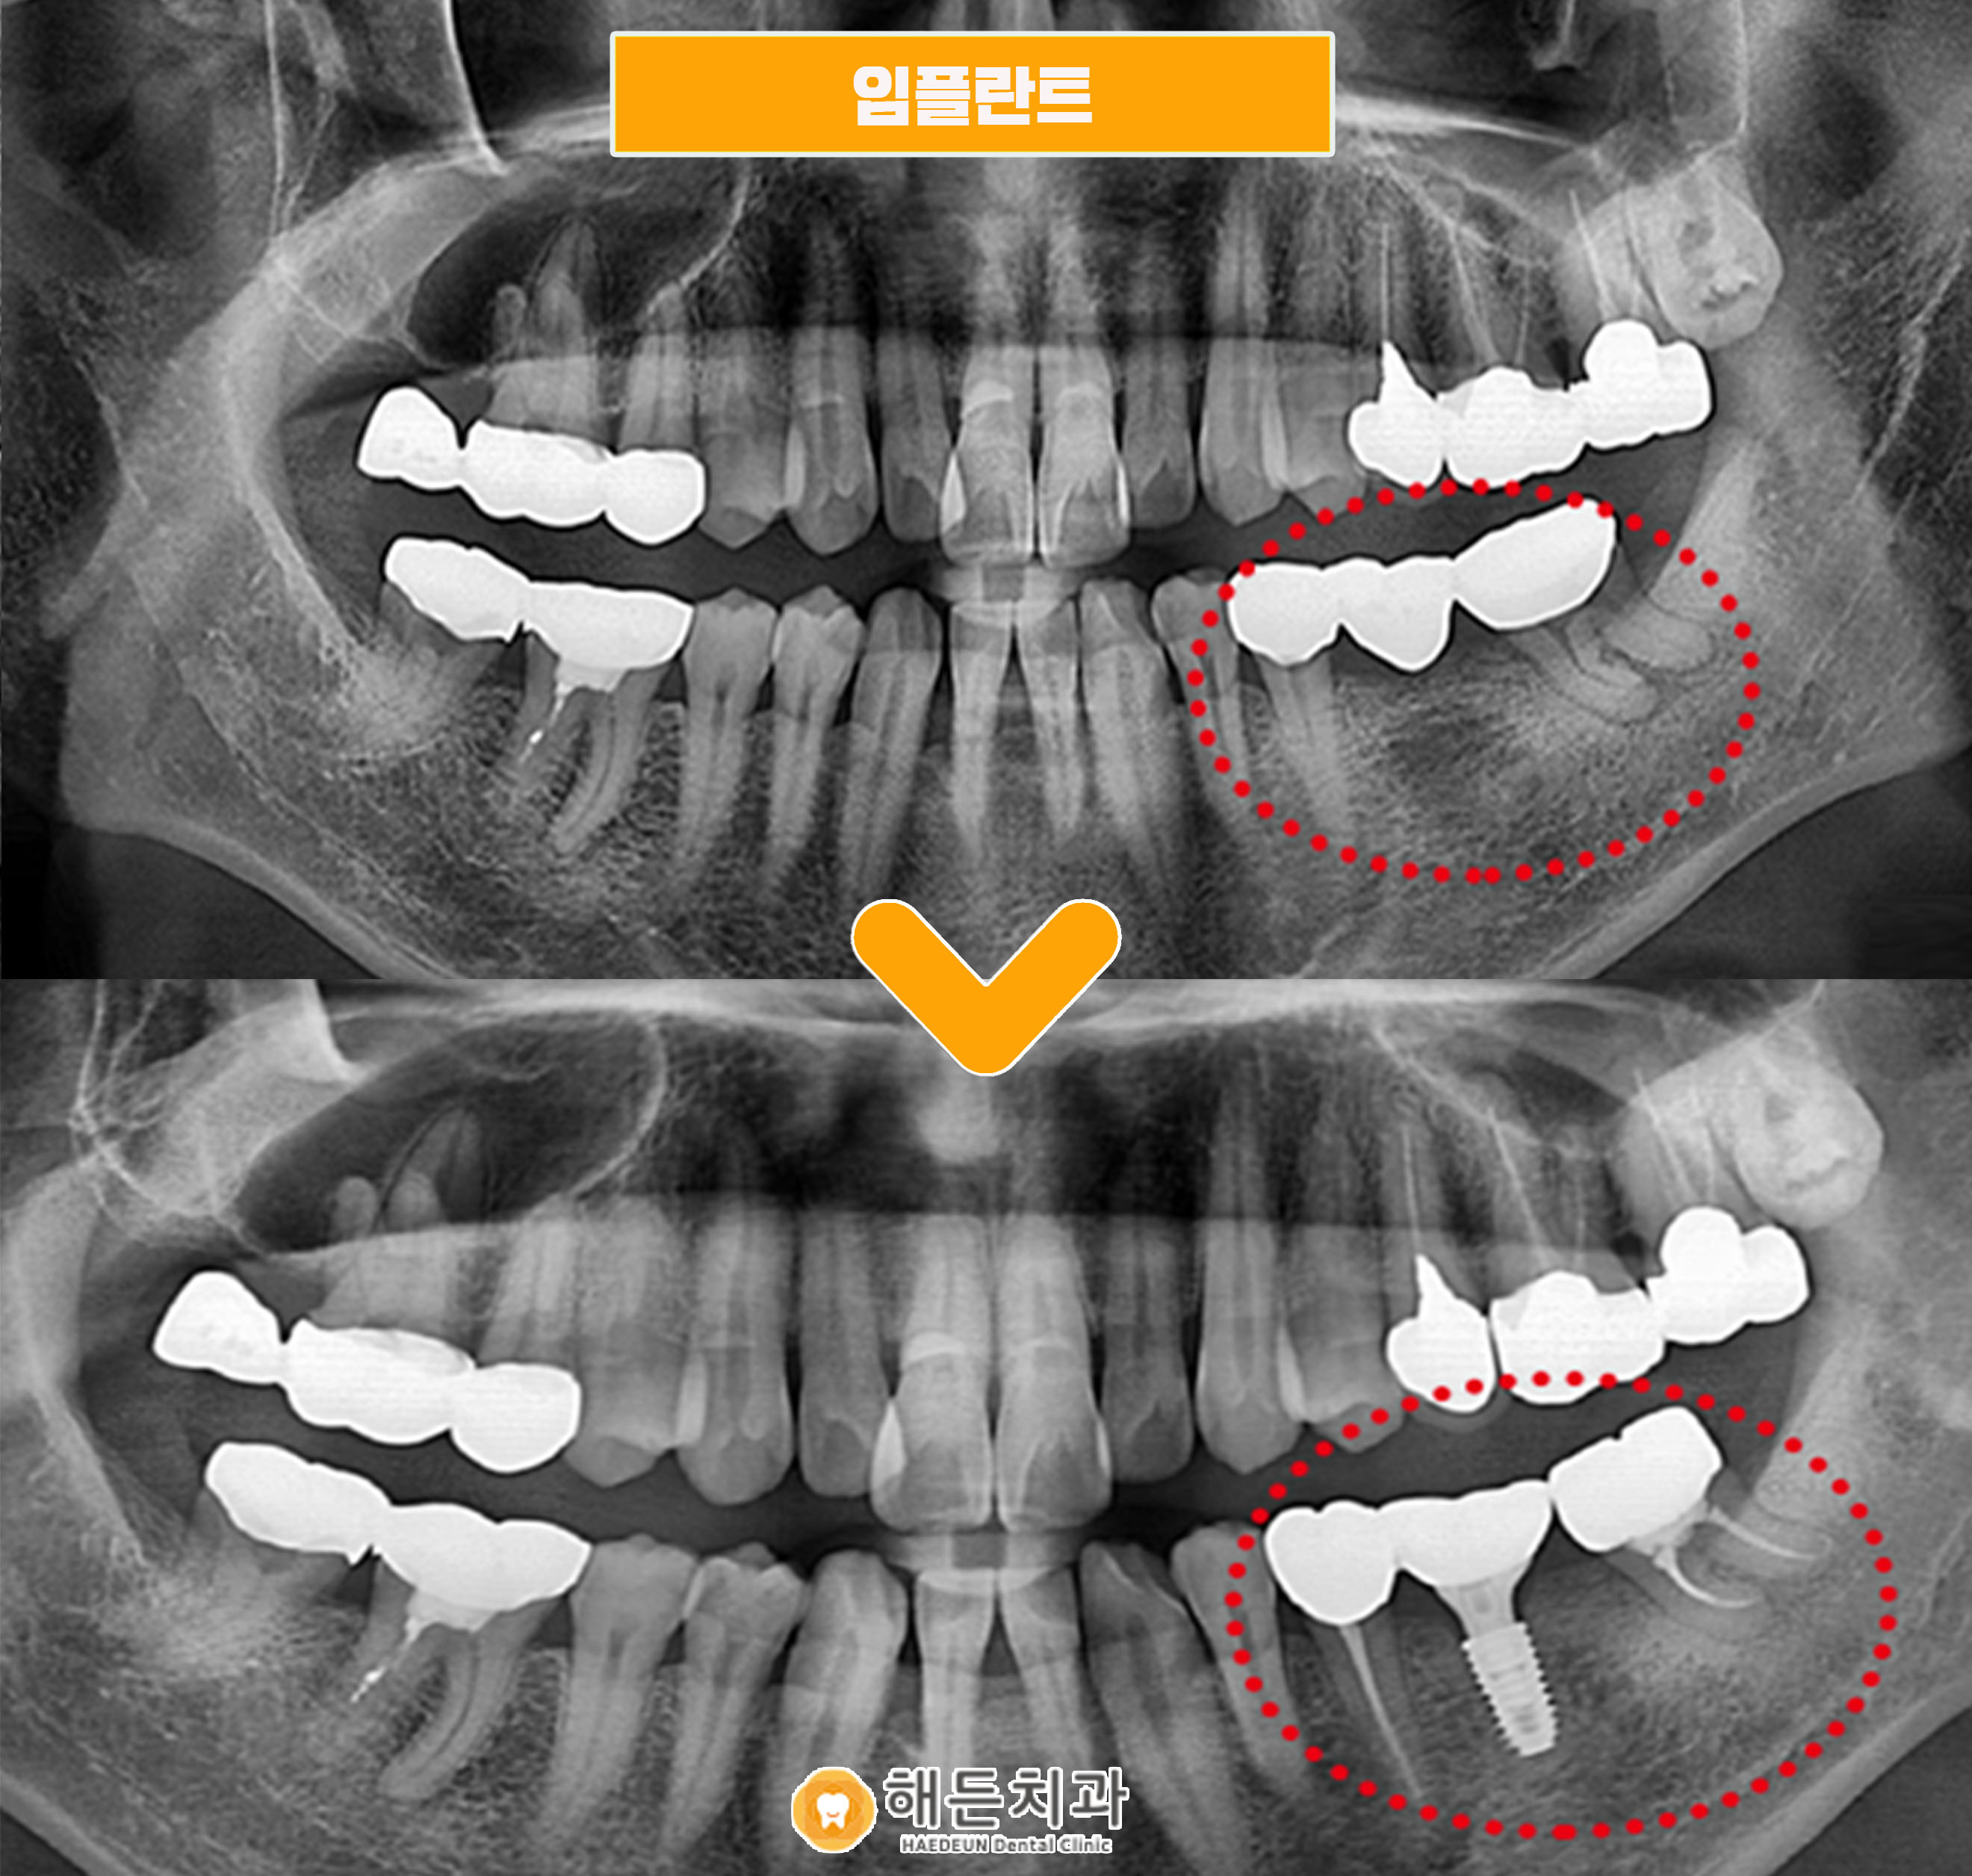

(치료기간 : 2023.12 ~ 2024.03)

해당 이미지는 임플란트 계획 수립을 위해

해든치과에 내원한 환자분의 엑스레이 자료로,

아래쪽 어금니 부위에 문제가 확인된 상태였습니다.

해당 환자분의 경우 기존에 브릿지로 연결된 상태였으며,

이를 제거한 이후 양쪽 치아는 상태에 따라

신경치료를 진행하는 방향을 고려했습니다.

가운데 결손 부위는 천안아산치과에서 임플란트로

보완하는 계획을 세우게 되었습니다.

신경치료와 임플란트 식립 과정을 거친 뒤,

최종 단계로 보철물을 장착한 모습입니다.

초기 진단부터 계획 수립까지의 과정을 바탕으로

해든치과에서 전체 치료가 마무리되었으며,

현재는 기능적인 회복과 외형적인 부분까지 함께

고려된 상태를 확인할 수 있습니다.